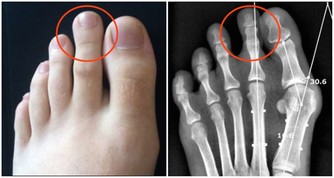

4.防癌抗癌。大蒜中的鍺、硒等,對腫瘤細胞和癌細胞有抑製作用。大蒜中還含有蒜臭素,能夠提高身體免疫力。